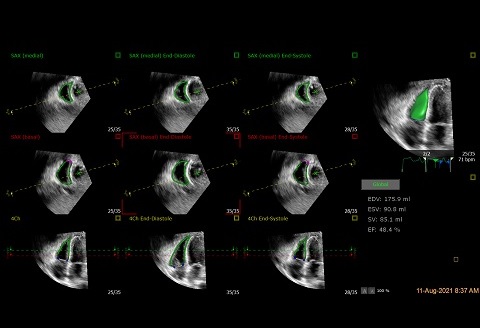

4D LV-ANALYSIS

2D画像を用いたStrain計測と比較して3D画像を用いたStrain計測は梗塞・虚血領域の範囲や拡張・収縮の時相のずれを全周性に観察することが可能です。